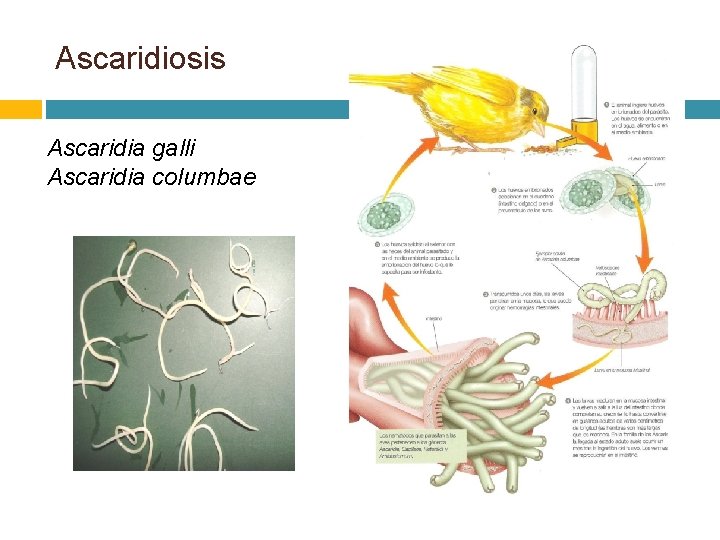

Ascaridiosis Ascaridia galli Ascaridia columbae

LOCALIZACION: el órgano predilecto es intestino delgado